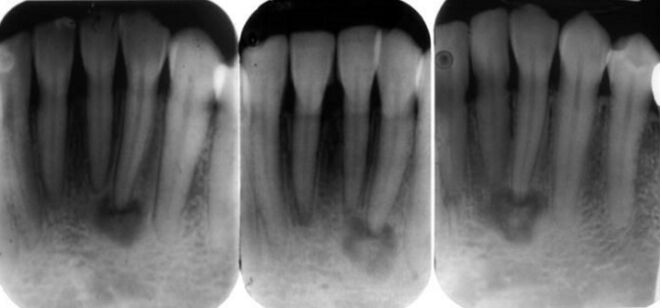

69.病人被診斷有牙周病,故每日清潔牙齒5次,每次皆用牙線清潔10分鐘。因牙齒對冷熱水敏感,就診時拍攝根尖X光片如下,其齒頸部異常為何? (A)磨耗(abrasion) (B)咬耗(attrition) (C)齒腐蝕(erosion) (D)內吸收(internal resorption)

70.病患因右邊牙齒對冷熱食物刺激有疼痛感而來檢查,臨床檢查發現牙齒顏色變化,根尖X光片如附圖,標示1 與2處最可能的診斷為何? (A)1為齲齒(dental caries);2為內吸收(internal resorption) (B)1為內吸收(internal resorption);2為齲齒(dental caries) (C)1、2皆為齲齒(dental caries) (D)1、2皆為內吸收(internal resorption)